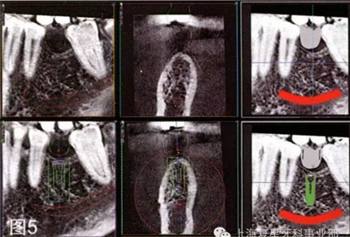

通過(guò)對(duì)牙冠的最后評(píng)估,考慮到重要的解剖結(jié)構(gòu),如下齒槽神經(jīng)和血管,設(shè)計(jì)種植體數(shù)字化的通過(guò)對(duì)牙冠的最后評(píng)估,考慮到重要的解剖結(jié)構(gòu),如下齒槽神經(jīng)和血管,設(shè)計(jì)種植體數(shù)字化的三維位置,獲得最便捷的修復(fù)和外科手術(shù)結(jié)果。然后將該虛擬設(shè)計(jì)的牙冠用于放射線模板(圖5)。

圖5:種植體的數(shù)字化三維位置的多面觀。注意如何用設(shè)計(jì)的虛擬冠作為數(shù)字化射線模板